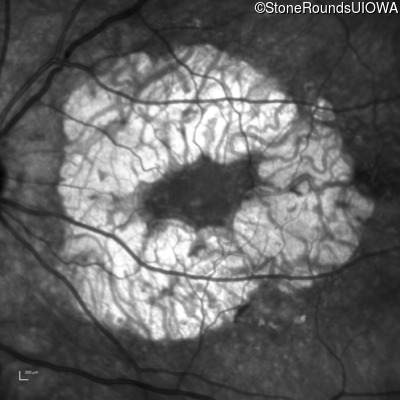

Infrared Fundus Photograph - Right - 20/32

Exemplar